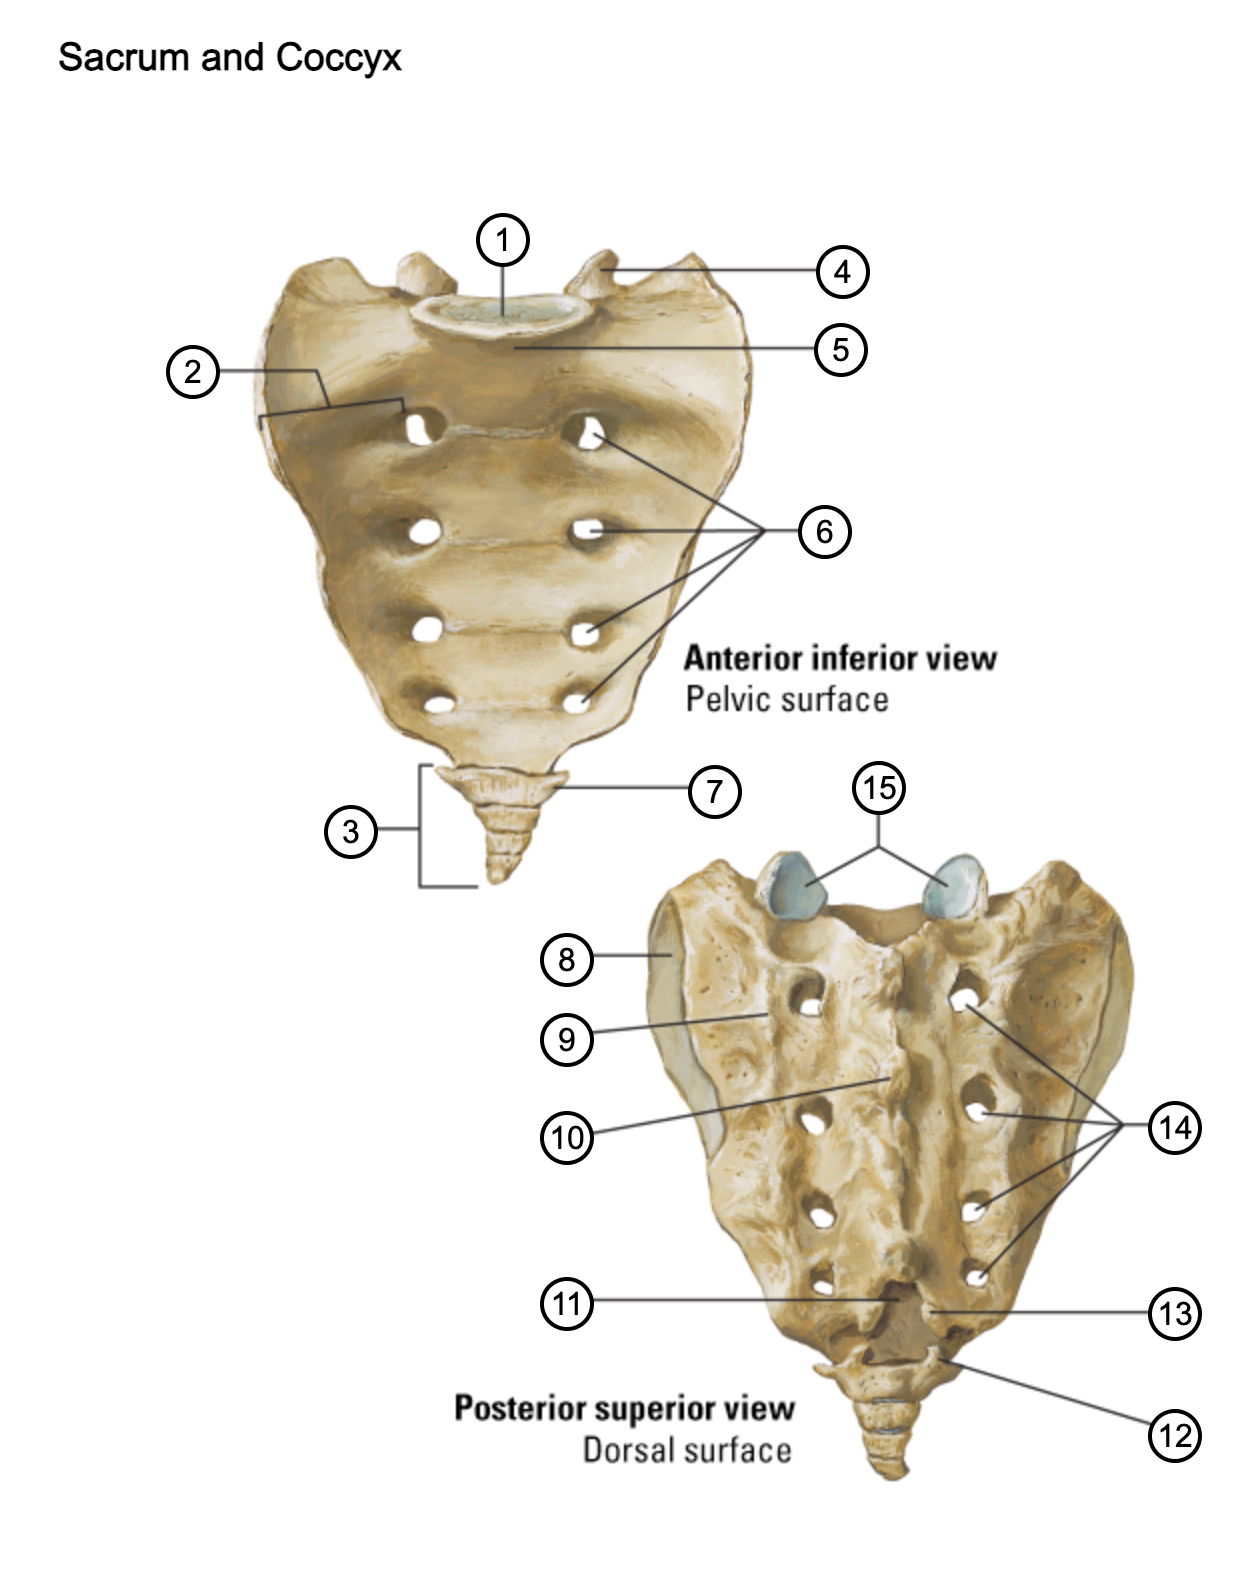

1

lumbosacral articular surface

2

ala of sacrum

3

coccyx

4

superior articular process

5

promontory

6

anterior sacral foramina

7

transverse process of coccyx

8

auricular surface

9

lateral sacral crest

10

median sacral crest

11

sacral hiatus

12

coccygeal horn

13

sacral horn

14

posterior sacral foramina

15

facets of superior articular processes